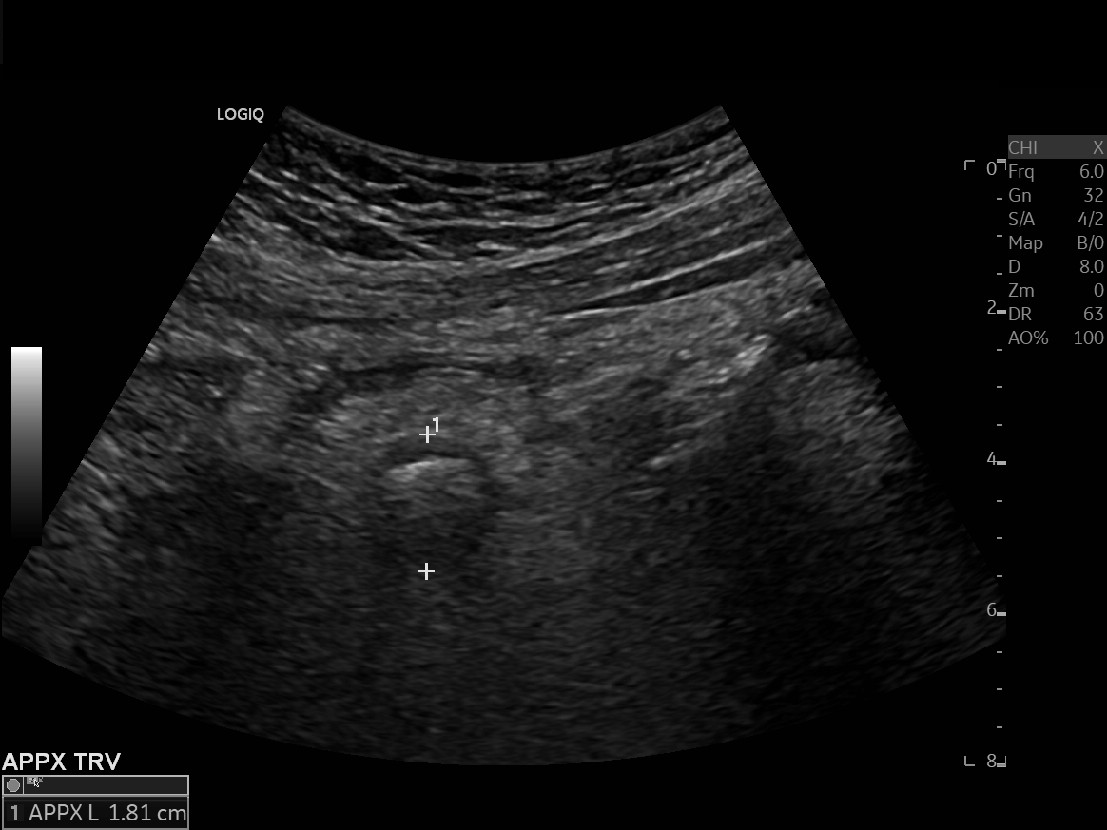

Appendicitis 19

Perforate appendicitis measuring 1.8 cm with interval abscess formation on follow up ultrasound imaging.